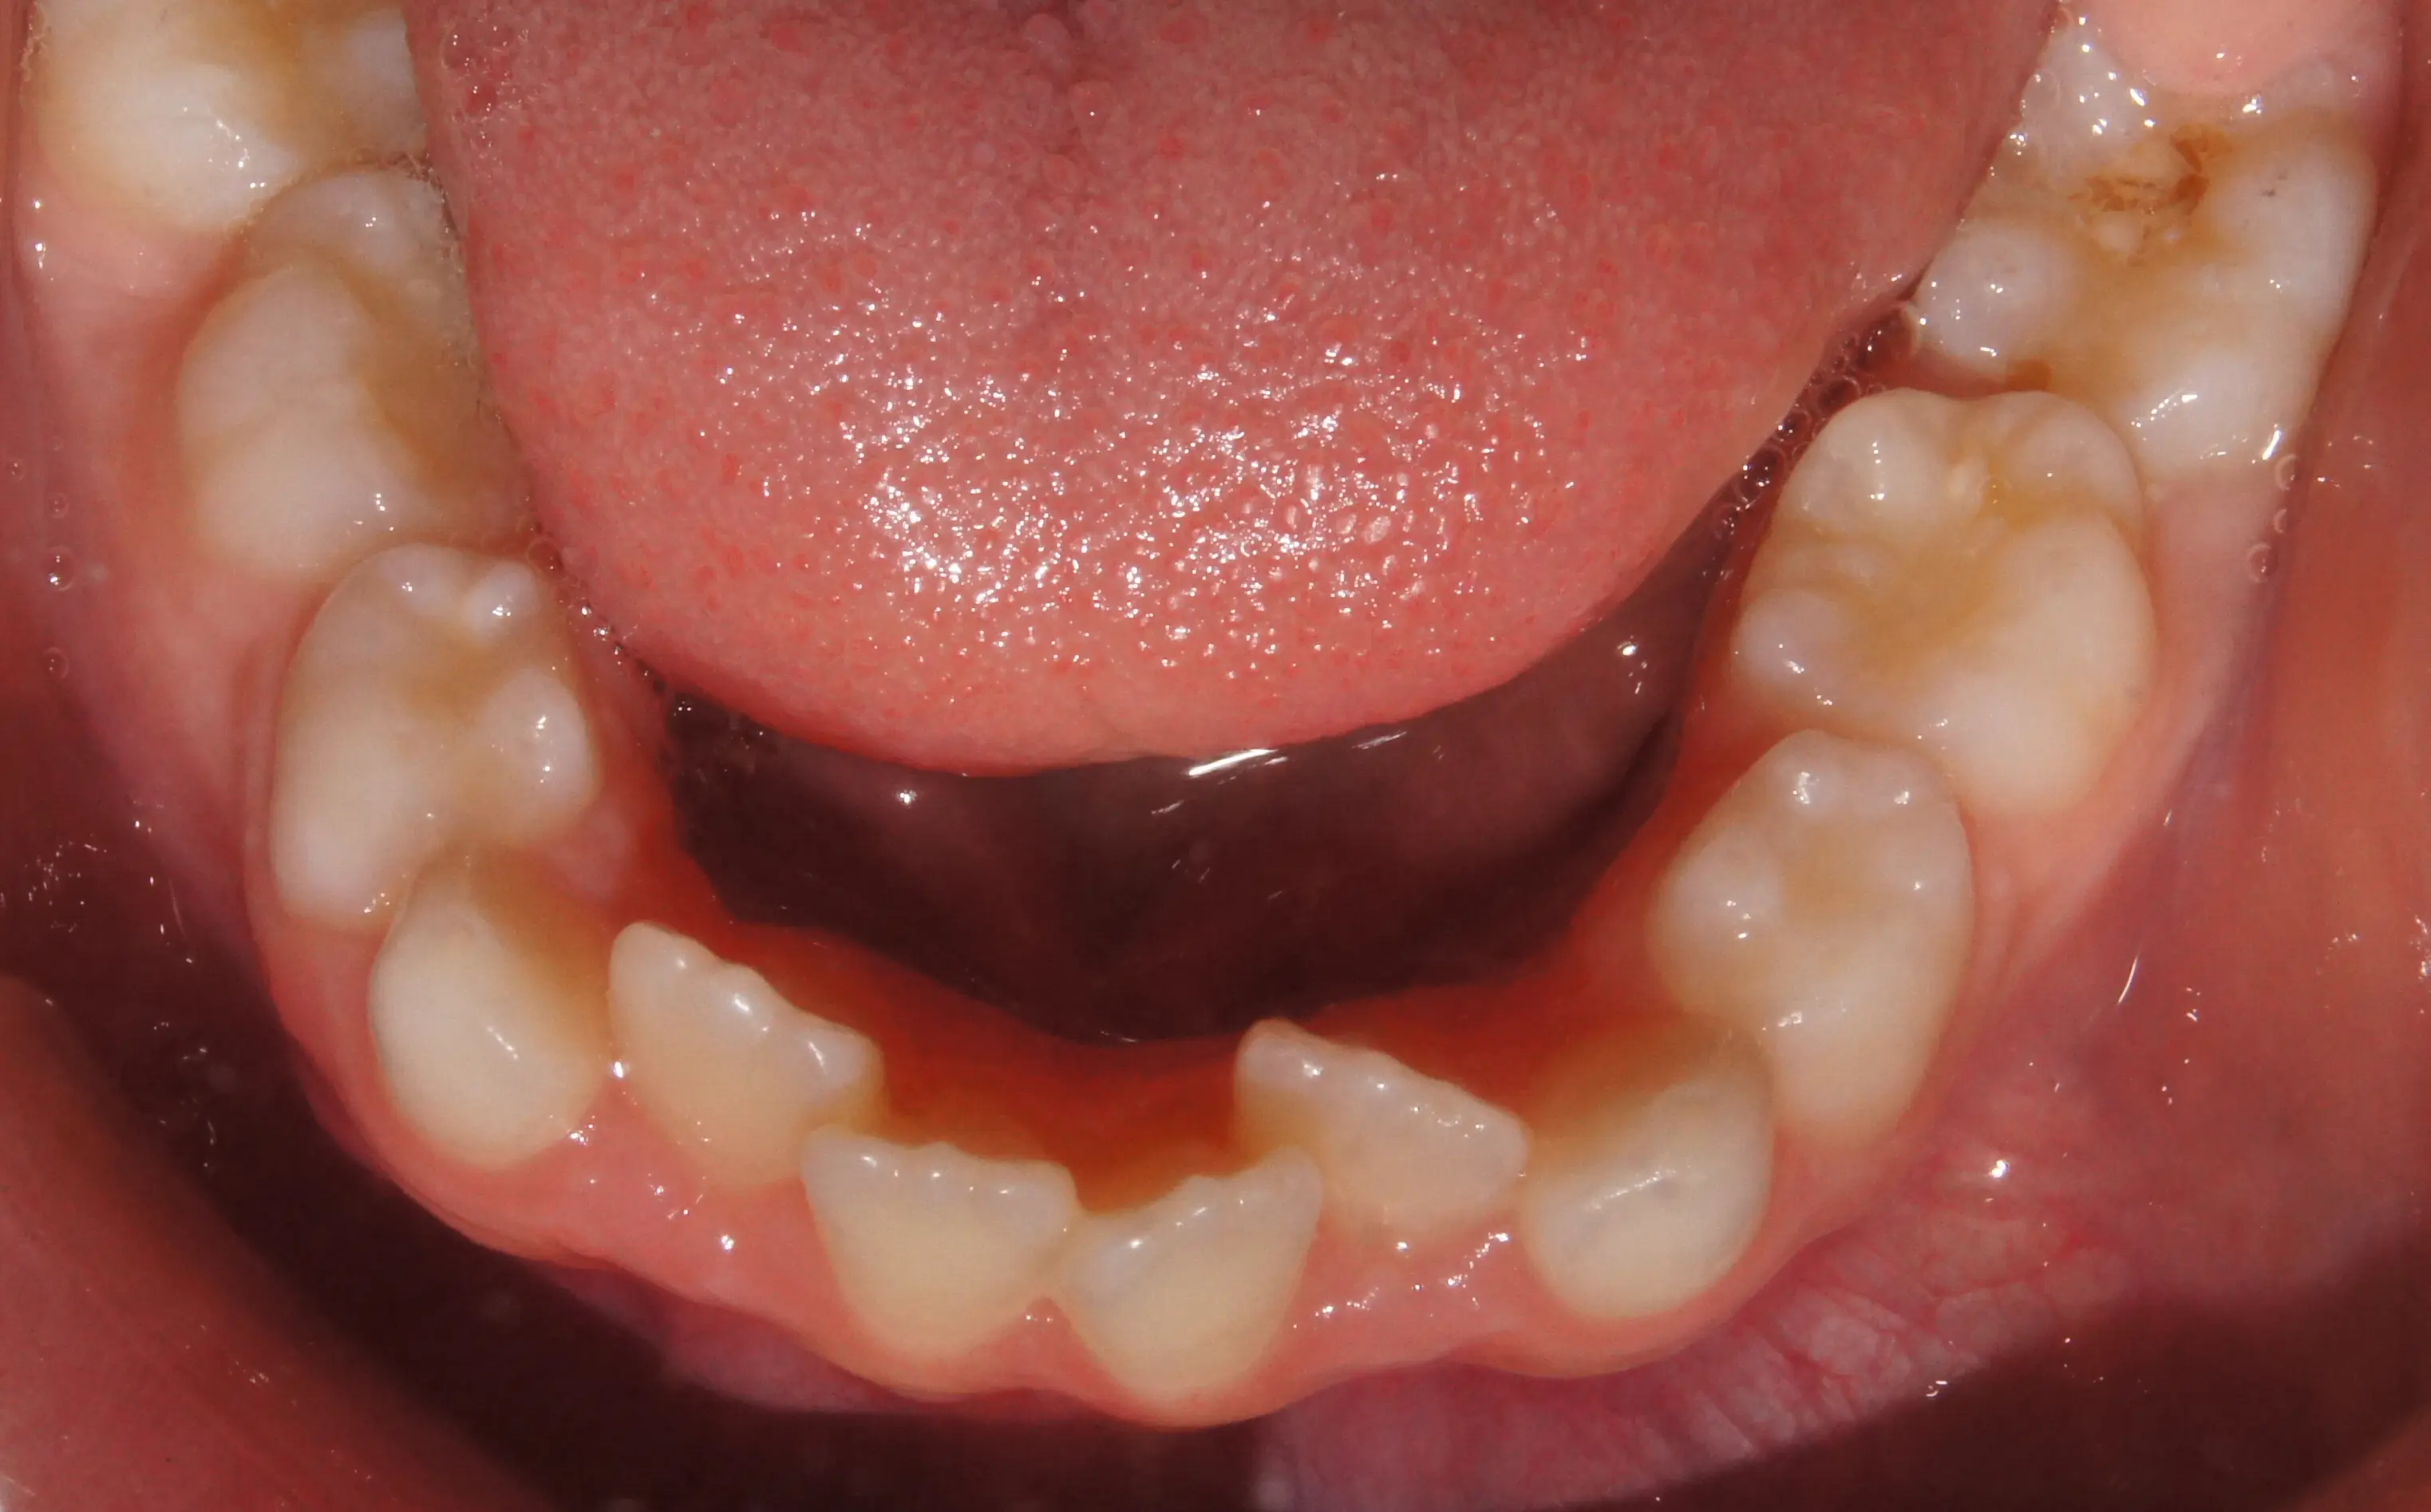

Early Crowding Harley Street Orthodontist London Bond Street Orthodontist Web 94 gloucester road, bishopston, bristol, bs7 8bn. As of 1 april 2021, the city had an. Brantford regional real estate assn inc 106 george street, brantford, ontario n3t 2y4. 82 bond street house for sale in cambridge, ontario for $599,900 cad, 3 bedrooms, 2 bathrooms, 1753 sqft. Founded in clifton by charles joseph hole in 1867, cj hole's main.. Bond Street Orthodontist.

Early Crowding Harley Street Orthodontist London Bond Street Orthodontist Founded in clifton by charles joseph hole in 1867, cj hole's main. 82 bond street house for sale in cambridge, ontario for $599,900 cad, 3 bedrooms, 2 bathrooms, 1753 sqft. Web citadel securities has quietly shelved plans to join one of wall street’s most prominent clubs: Web 94 gloucester road, bishopston, bristol, bs7 8bn. The ranks of bond dealers. Brantford. Bond Street Orthodontist.